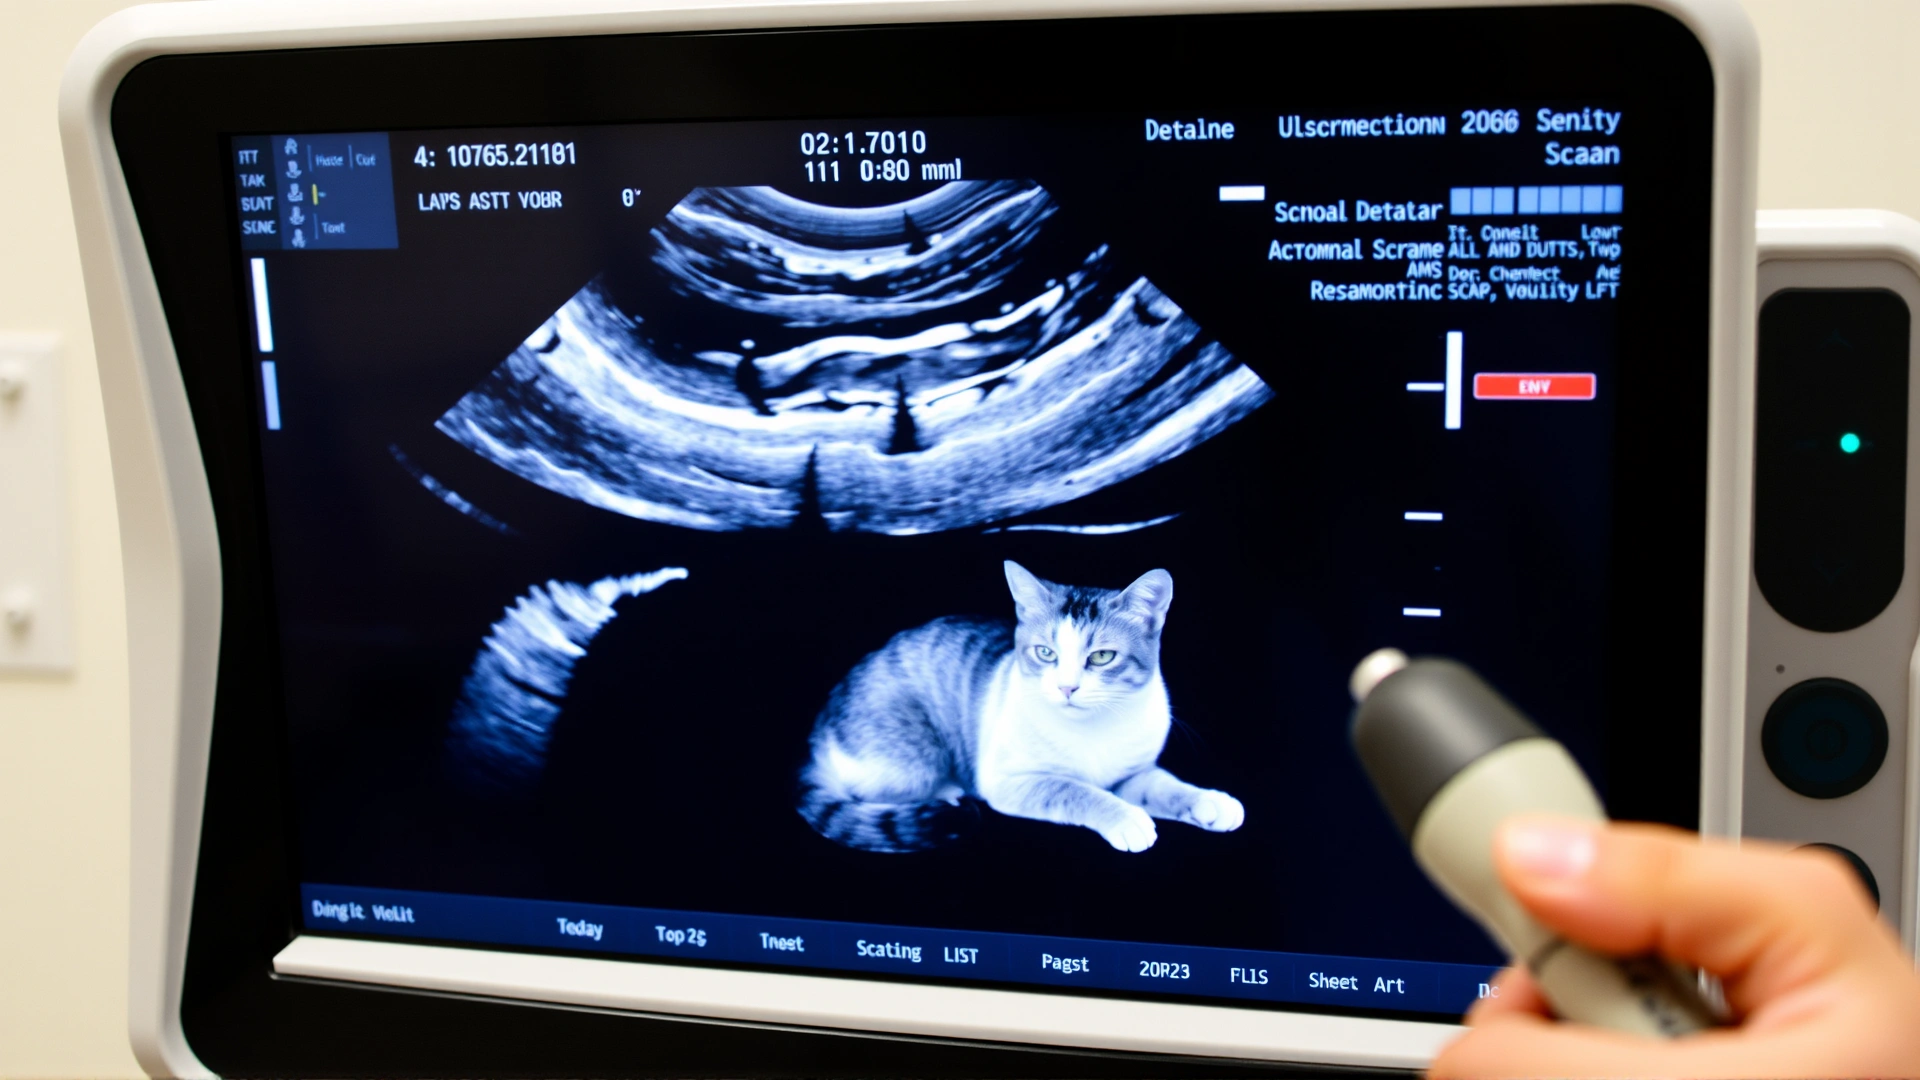

3. تقنيات التصوير

تُستخدم لتحديد مدى انتشار الورم:

- الأشعة السينية للصدر لبحث النقيلات الرئوية.

- الألتراساوند للبطن لتقييم العقد اللمفاوية والأعضاء الداخلية.

- التصوير المقطعي (CT) لتخطيط الجراحة بدقة.